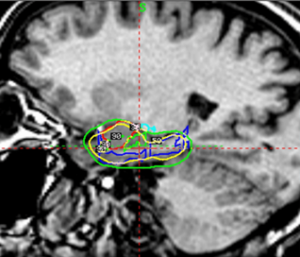

With this CE marking, healthcare providers in regions recognizing EU regulatory standards can now offer Esprit as a precision alternative to open neurosurgery for carefully selected epilepsy cases. Esprit’s demonstrated submillimeter accuracy and highly targeted dose delivery make it uniquely suited to treat epileptogenic zones while minimizing exposure to healthy brain tissue, an essential advantage for patients seeking effective treatment with fewer side effects.